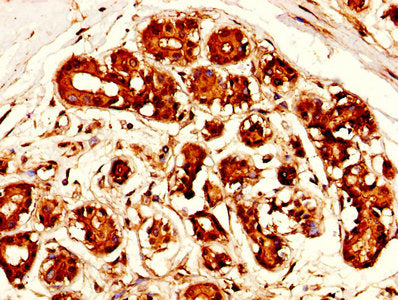

IHC image of the antibody diluted at 1:300 and staining in paraffin-embedded human ovarian cancer performed on a Leica BondTM system. After dewaxing and hydration, antigen retrieval was mediated by high pressure in a citrate buffer (pH 6.0). Section was blocked with 10% normal goat serum 30min at RT. Then primary antibody (1% BSA) was incubated at 4°C overnight. The primary is detected by a biotinylated secondary antibody and visualized using an HRP conjugated SP system.

IHC image of MSLN Antibody diluted at 1:300 and staining in paraffin-embedded human breast cancer performed on a Leica BondTM system. After dewaxing and hydration, antigen retrieval was mediated by high pressure in a citrate buffer (pH 6.0). Section was blocked with 10% normal goat serum 30min at RT. Then primary antibody (1% BSA) was incubated at 4°C overnight. The primary is detected by a biotinylated secondary antibody and visualized using an HRP conjugated SP system.